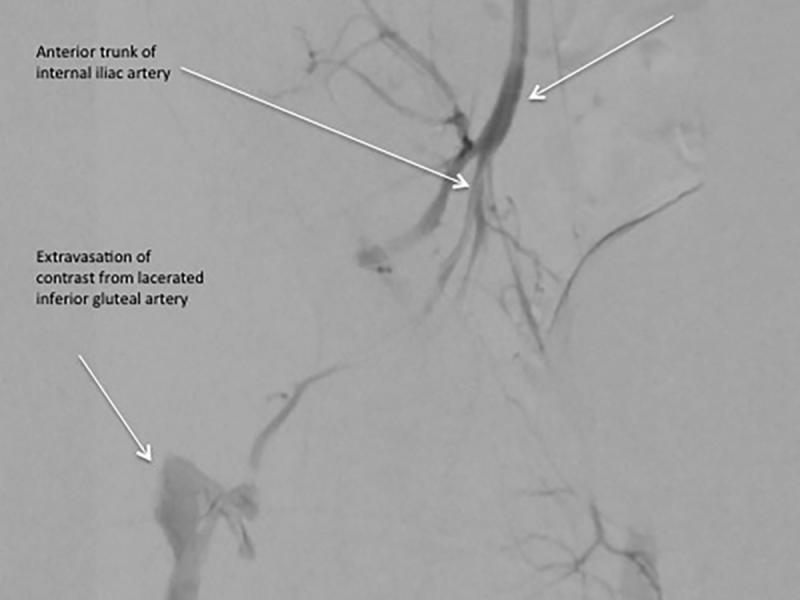

Critical Cases - Active Gluteal Muscle Internal Hemorrhage!

History 68 yo male hx of atrial fibrillation on apixaban